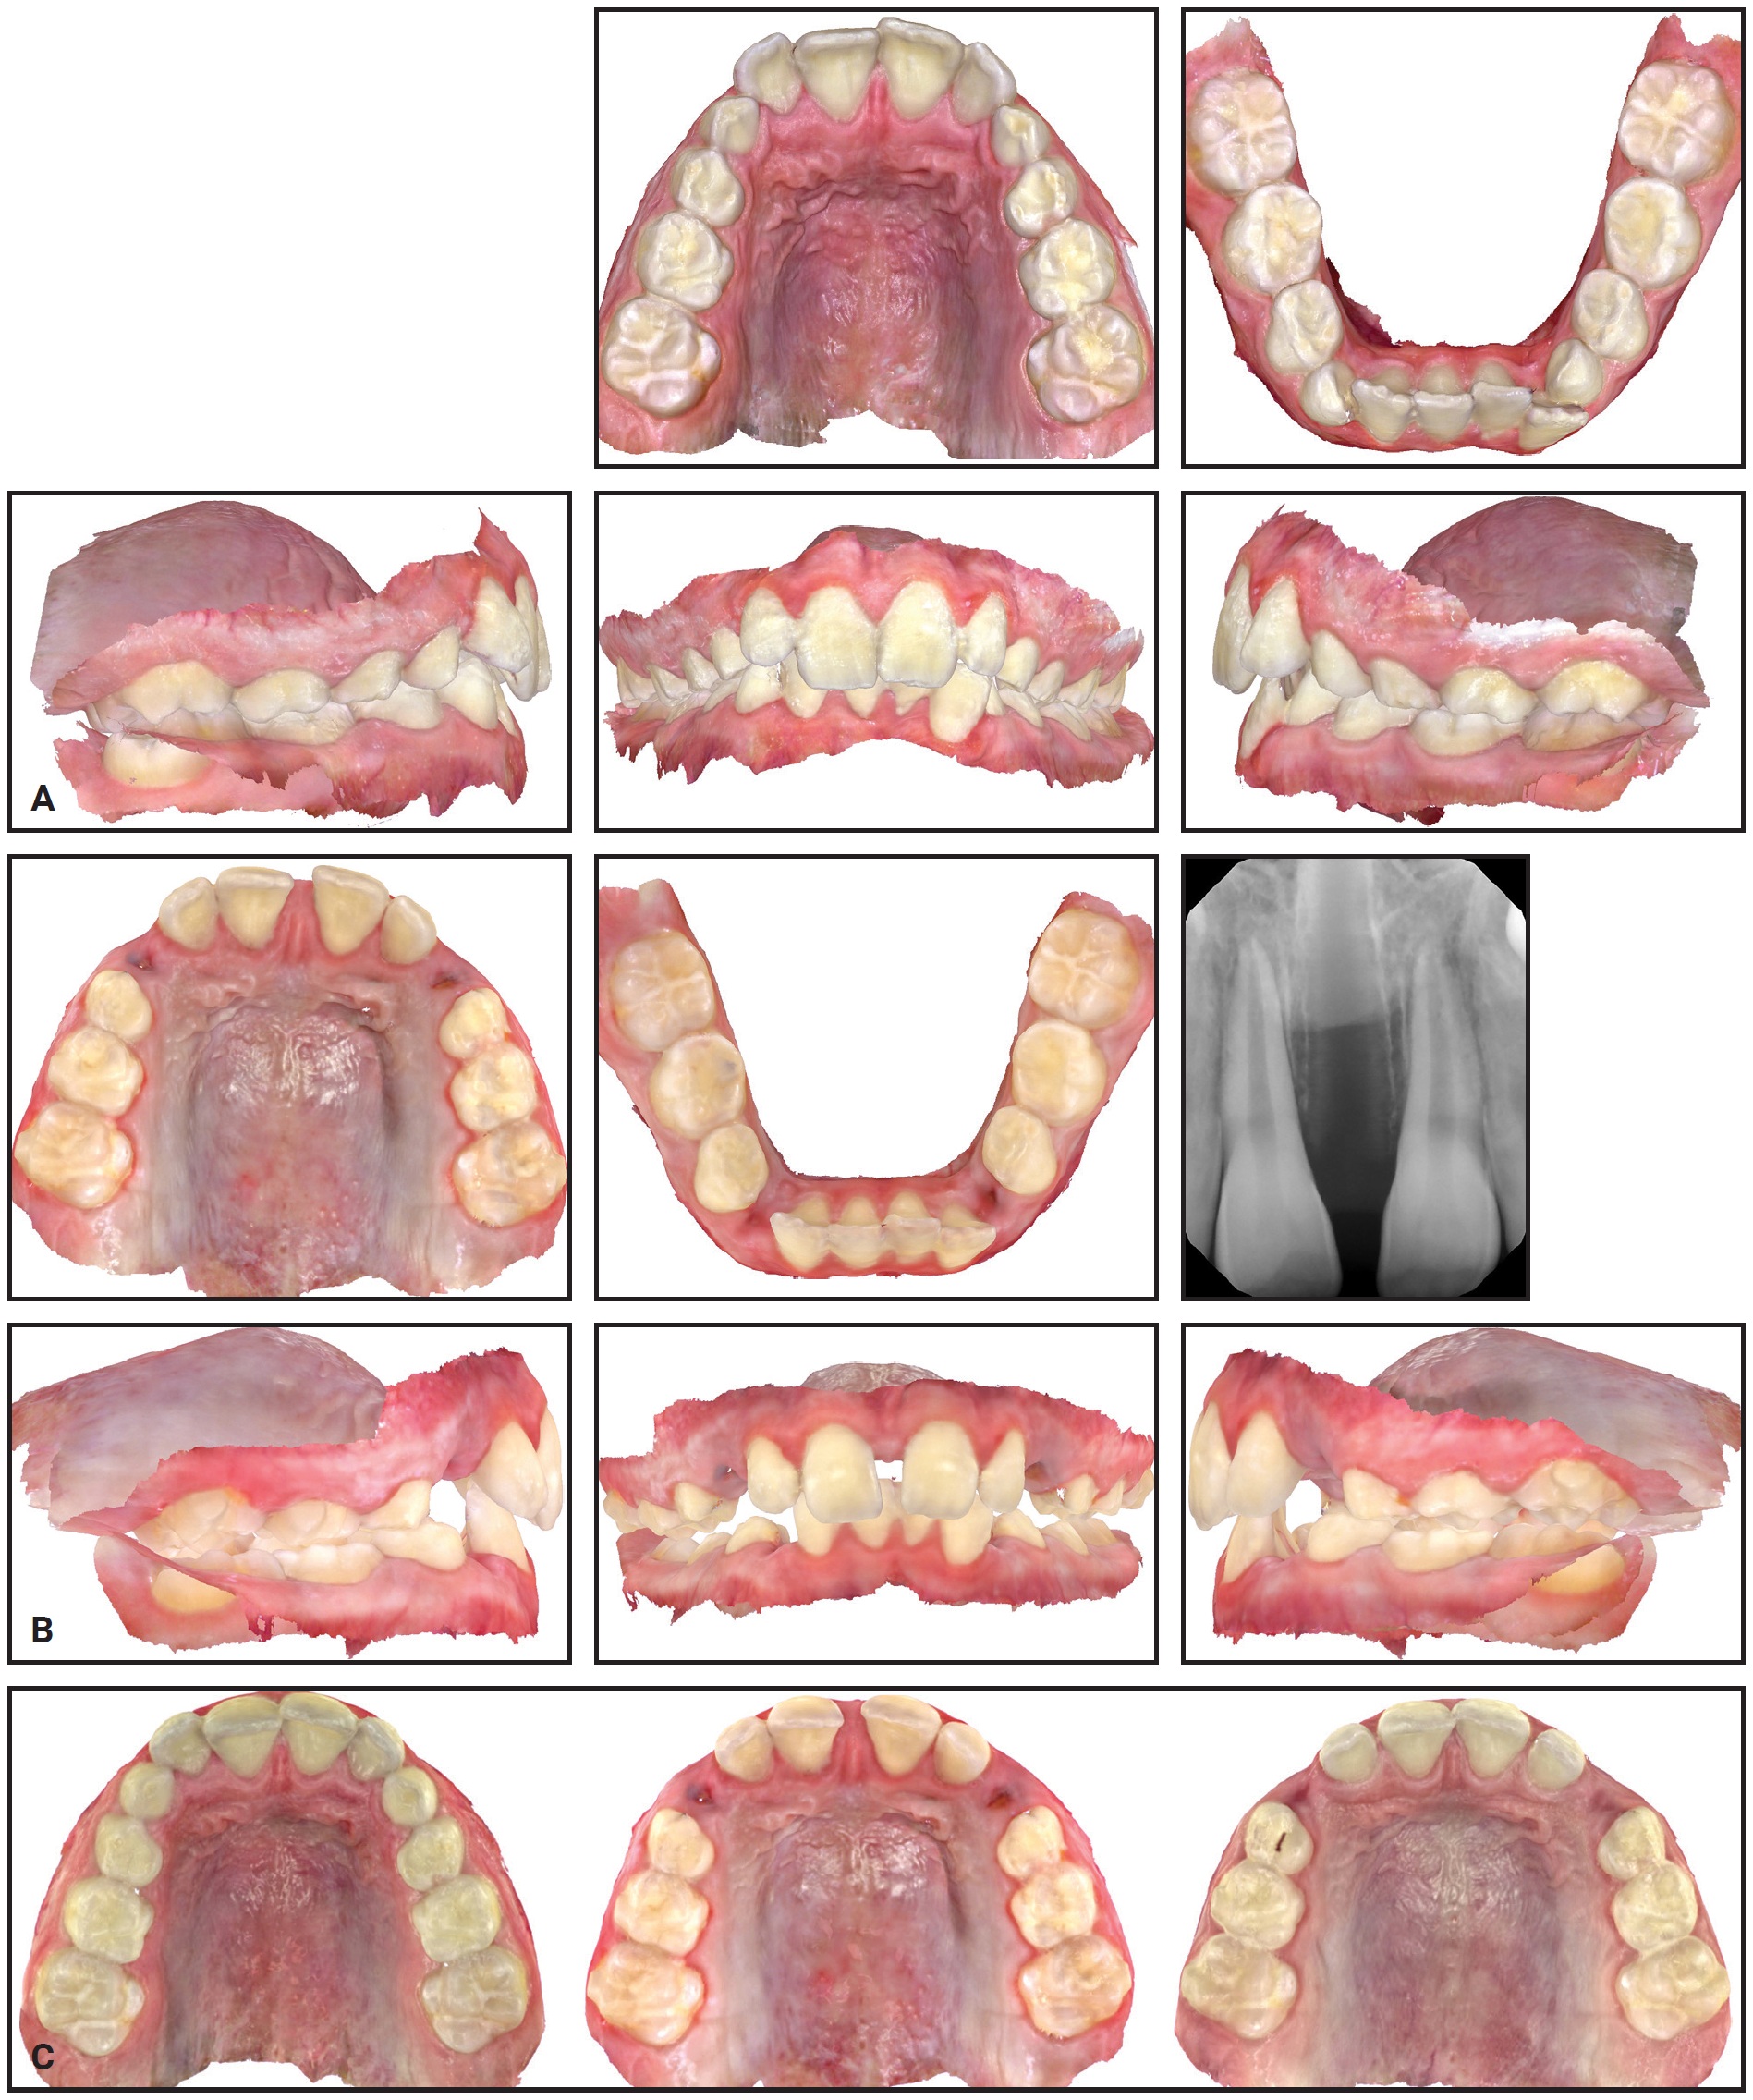

A 9-year-old male presented with the chief concerns of crowding and potentially blocked-out canines (Fig. 4). Palatal expansion and extraction of all deciduous canines were recommended as a first phase of treatment. Eventual alignment of the upper anterior teeth was planned to open space for the upper permanent canines, in the hope that they would erupt spontaneously. The lower arch was to be monitored for later use of the leeway space to resolve the lower crowding during comprehensive treatment.

A series of 34 IPEs was prescribed, to be changed daily. Upon completion of the expansion, the patient was scanned for holding expanders, which were worn for six months as the suture matured.

Fig. 4 Case 1. A. At beginning of treatment. B. After 33 of 34 stages of expansion with IPE. C. Progress of expansion: beginning of treatment (left), after expansion (center), and after four months of retention (right).